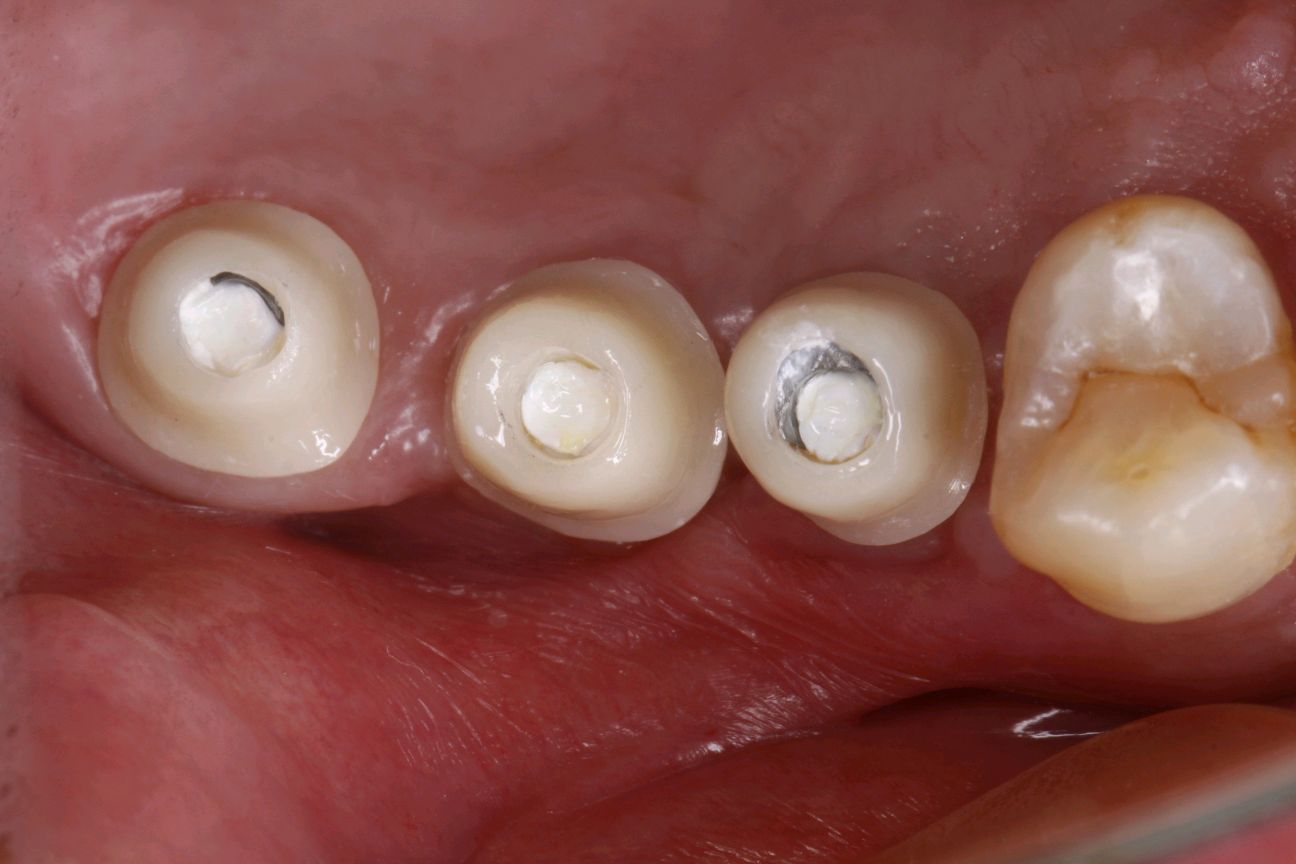

种植二期,拍片检查

旋出愈合帽,局部冲洗吹干。在就位导板的引导下旋入种植基台,拍片确认基台到位。全瓷冠试戴,冠边缘密合性良好,邻接良好。